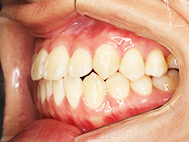

Before

| 症状 | 上下前歯叢生 |

| 治療内容 | 上顎部分裏側矯正 下顎は目立ちにくい透明な装置 |

| 治療期間 | 11ヶ月 |

| 費用 | 620,000円 ※最新の治療費についてはご確認ください |

左上の前歯内側に入っている下の前歯ガチャ歯

左上前歯が下の歯の内側に入っているのが気になるとの事で来院されました。目立たない矯正治療を希望しているとのこでした。 上顎の装置は、歯の裏側(リンガル装置)で下顎は表側で矯正治療を行いました。口を閉じた時、上の前歯が内側に入っている為に下の歯を前に押し出している状態でした。その為、上の歯を前に出すだけではその歯が下とのかみ合わせの関係で、前に飛び出すような治療となってしまいます。 今回の症例ではシュミレーションを見て頂き、下の歯も治療し、内側へ下げることによって上の歯も飛びだすことなく、キレイにおさまることを説明し、上下一緒に矯正することをお勧めさせて頂きました。